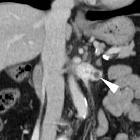

Asymptomatic

left renal vein aneurysm with thrombosis. CT performed for unrelated reasons detected a well-demarcated roundish lesion (arrowheads) abutting the left renal vein (*), measuring approximately 15 Hounsfield Units (HU) attenuation on unenhanced images.